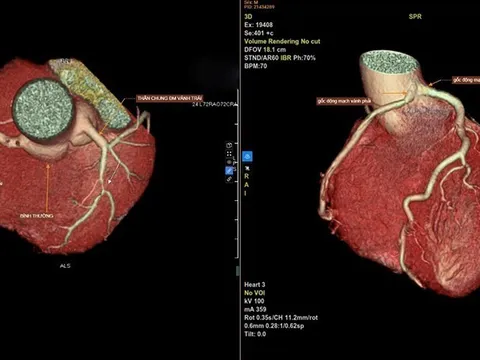

Khi huyết áp tăng vọt, mạch máu não có thể vỡ, gây liệt nửa người hoặc tử vong. Áp lực cao kéo dài cũng làm tổn thương lớp nội mạc mạch máu, khiến mảng xơ vữa bong ra, gây tắc nghẽn động mạch vành, hậu quả là cơn nhồi máu cơ tim cấp. Trái tim phải làm việc quá sức, phì đại dần và cuối cùng suy yếu: theo Framingham Heart Study, tăng huyết áp chiếm tới 75% nguyên nhân suy tim ở người cao tuổi.